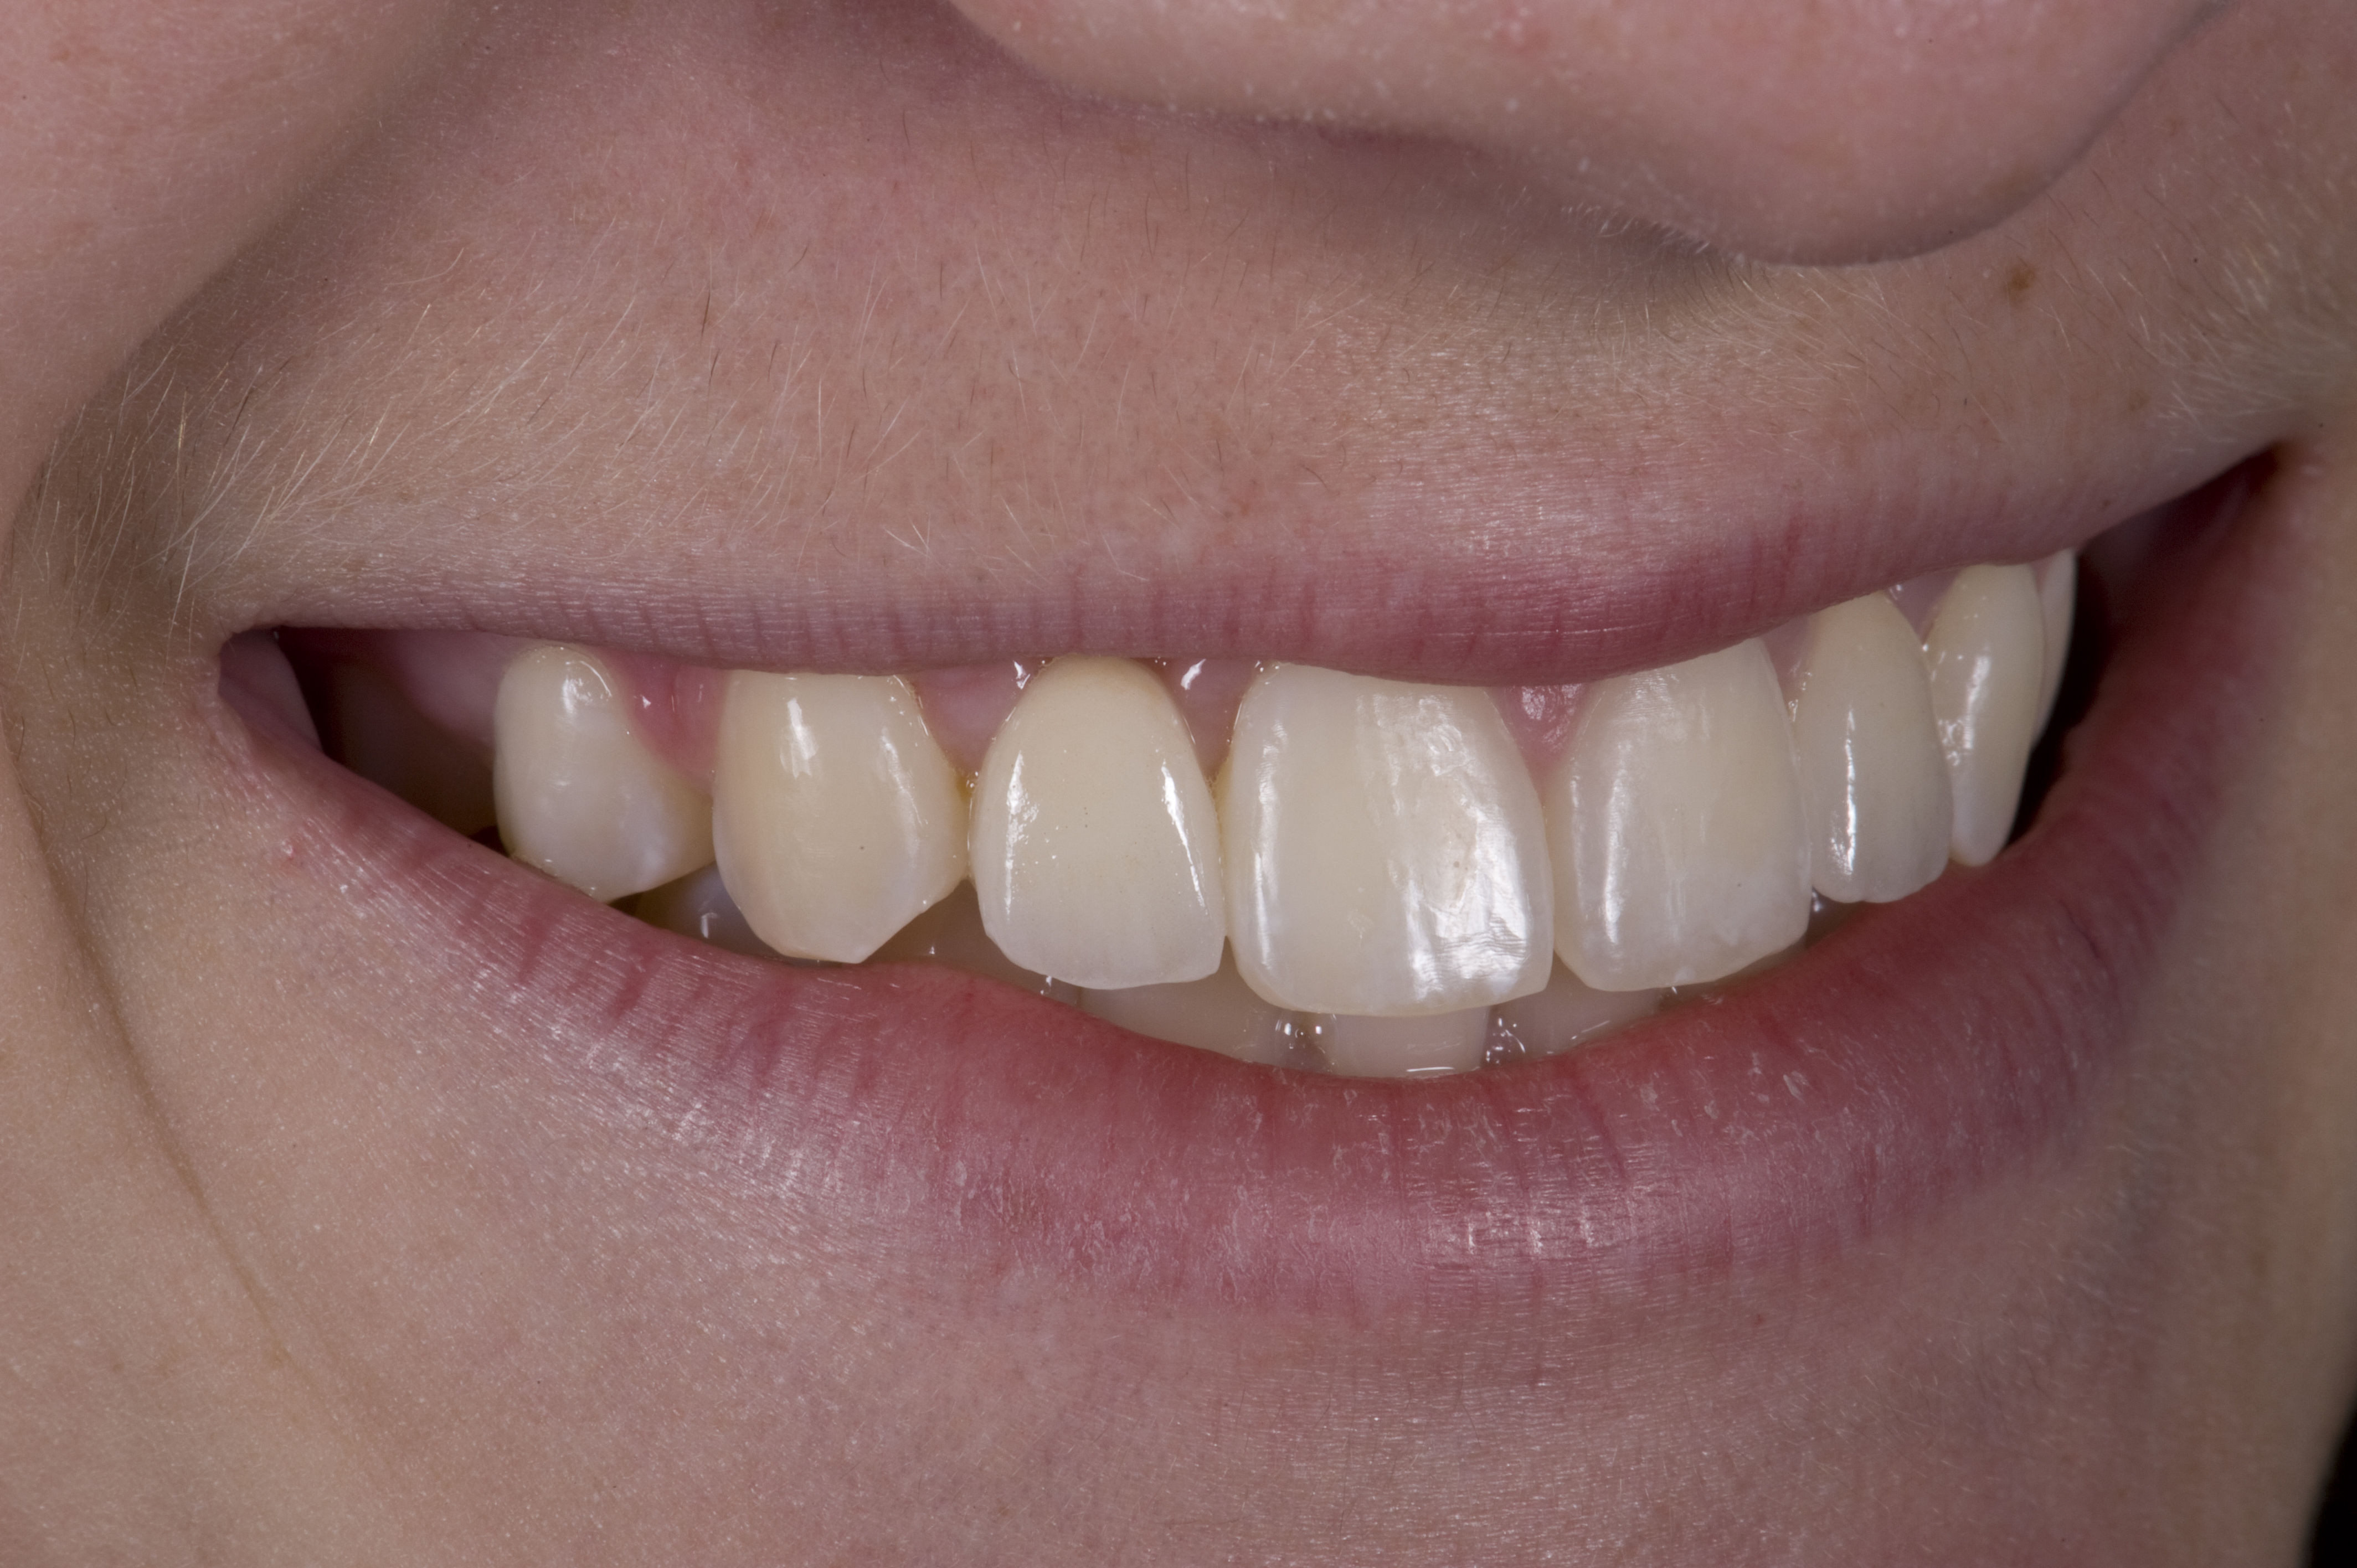

(12.) 15-year-old girl after orthodontic therapy idealized maxillary lateral incisor spaces.

Figure 12

(13.) Deficient ridges in the areas of the missing lateral incisors.

Figure 13

(14.) Occlusal view. Some form of augmentation would be needed if implants were being considered.

Figure 14

Some patients do not want an implant due to the need for surgical intervention, and others may not have enough space for implant placement. A 15-year-old patient presented to the office after completion of orthodontic treatment to idealize the spacing of her teeth and improve her occlusal relationship (Figure 12 through Figure 14). Because both of her maxillary lateral incisors were missing, the patient was wearing a retainer with lateral incisor pontics. She had a busy school schedule, but expressed her desire for a fixed restorative option. All of her options were discussed, and the patient was informed that if she wanted an implant, she would have to wait for at least 3 to 4 years for completion of growth. The patient was not sure if or when she wanted to have an implant placed in the future, especially considering her busy schedule and desire to attend college after high school. Considering her age and the need to be conservative, a single-wing zirconia Maryland Bridge was chosen as the ideal prosthetic replacement option. Because bonding a non-etchable and smooth surface such as zirconia requires chemical adhesion, it was decided to use a modified technique to make the bridge more retentive. One of the ways to improve adhesion of a zirconia bridge is to use an etchable feldspathic ceramic layer on the internal surface of the zirconia retainer.56-58 Unfortunately, it can be difficult to determine the thickness of the ceramic and ensure accurate seating of the restoration.